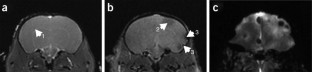

Many of the 5,500 threatened species of vertebrates found worldwide are highly protected and generally unavailable for scientific investigation. Here we describe a noninvasive protocol to visualize the structure and size of brain in postmortem specimens. We demonstrate its utility by examining four endangered species of kiwi (Apteryx spp.). Frozen specimens are thawed and imaged using MRI, revealing internal details of brain structure. External brain morphology and an estimate of brain volume can be reliably obtained by creating 3D models. This method has facilitated a comparison of brain structure in the different kiwi species, one of which is on the brink of extinction. This new approach has the potential to extend our knowledge of brain structure to species that have until now been outside the reach of anatomical investigation.

Corfield, J., Wild, J., Cowan, B. et al. MRI of postmortem specimens of endangered species for comparative brain anatomy. Nat Protoc 3, 597–605 (2008). https://doi.org/10.1038/nprot.2008.17